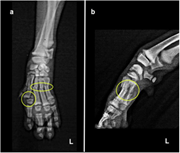

The management of metacarpal fractures can be either conservative, following a closed reduction and coaptation approach, or surgical where multiple techniques have been described including either internal or external fixation or a combination of both.6,7 To date, there is no consensus in the veterinary literature on which approach should be preferred.3 but general considerations when deciding the approach include the age of the animal, the type of the fractures, the extend of the bone and soft tissue damage, whether the fractures are open or closed, the presence of infection in old fractures and the concurrent presence of fractures in neighbouring bones.3‒6 In this case the closed reduction and coaptation technique was elected, as described by various authors for single or dual metacarpal fractures.4‒8 but modified due to fractures present on all metacarpals (Figure 1). The animal was placed on Sternal recumbency under deep anaesthesia. An Allis tissue forceps was placed on the nail of the 2nd digit and one on the nail of the 4th digit and the ends of the forceps were tied to a steady point on the wall via a traction rope in order to achieve better distribution of the traction force on all digits, whilst making certain that the limb and rope are on a straight line and exactly parallel to the table surface. Gentle and steady distal-to-proximal traction was applied on the limb with the surgeon’s left hand placed right proximally to the carpus while the right hand applied lateral-to-medial pressure on the metacarpal area in order to achieve axonal alignment. Under traction, a modified Robert-Jones splint was applied to provide stabilization. Postoperative radiographs showed good fracture reduction and alignment (Photo 2). Very strict rest was advised for 7days postoperatively and pain management was continued at home with carprofen at 4mg/kg orally once daily for 18 days. Gradual increase in exercise was advised after day 7 to encourage use of the limb and assist fracture healing. The splint was inspected on the 3rd and 12th day postoperatively for any signs of dressing complications such as vascular compromise of the limb or pressure-dermatitis, with no signs of complications. Conscious radiographs taken 18days postoperatively (Photo 3) revealed healing of the fractures and the animal was confident in using the limb with no indication of lameness. The splint was removed at day 20 and a small course of physiotherapy was followed for 2weeks due to moderate postoperative muscle atrophy. Follow-ups at 6 weeks and 3months after reduction, confirmed full recovery and return to normal activity.

Photo 2 Dorsopalmar radiograph after closed reduction.